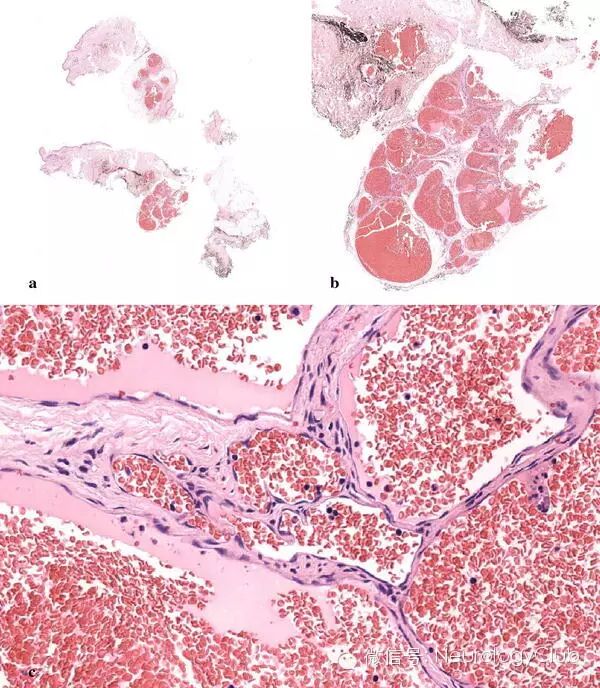

(a:海绵状血管瘤:皮下组织可见边界清楚的血管增生,由众多扩张的血管组成[全景];b:原图×2;c:海绵状血管瘤:薄壁血管和扁平内皮×37